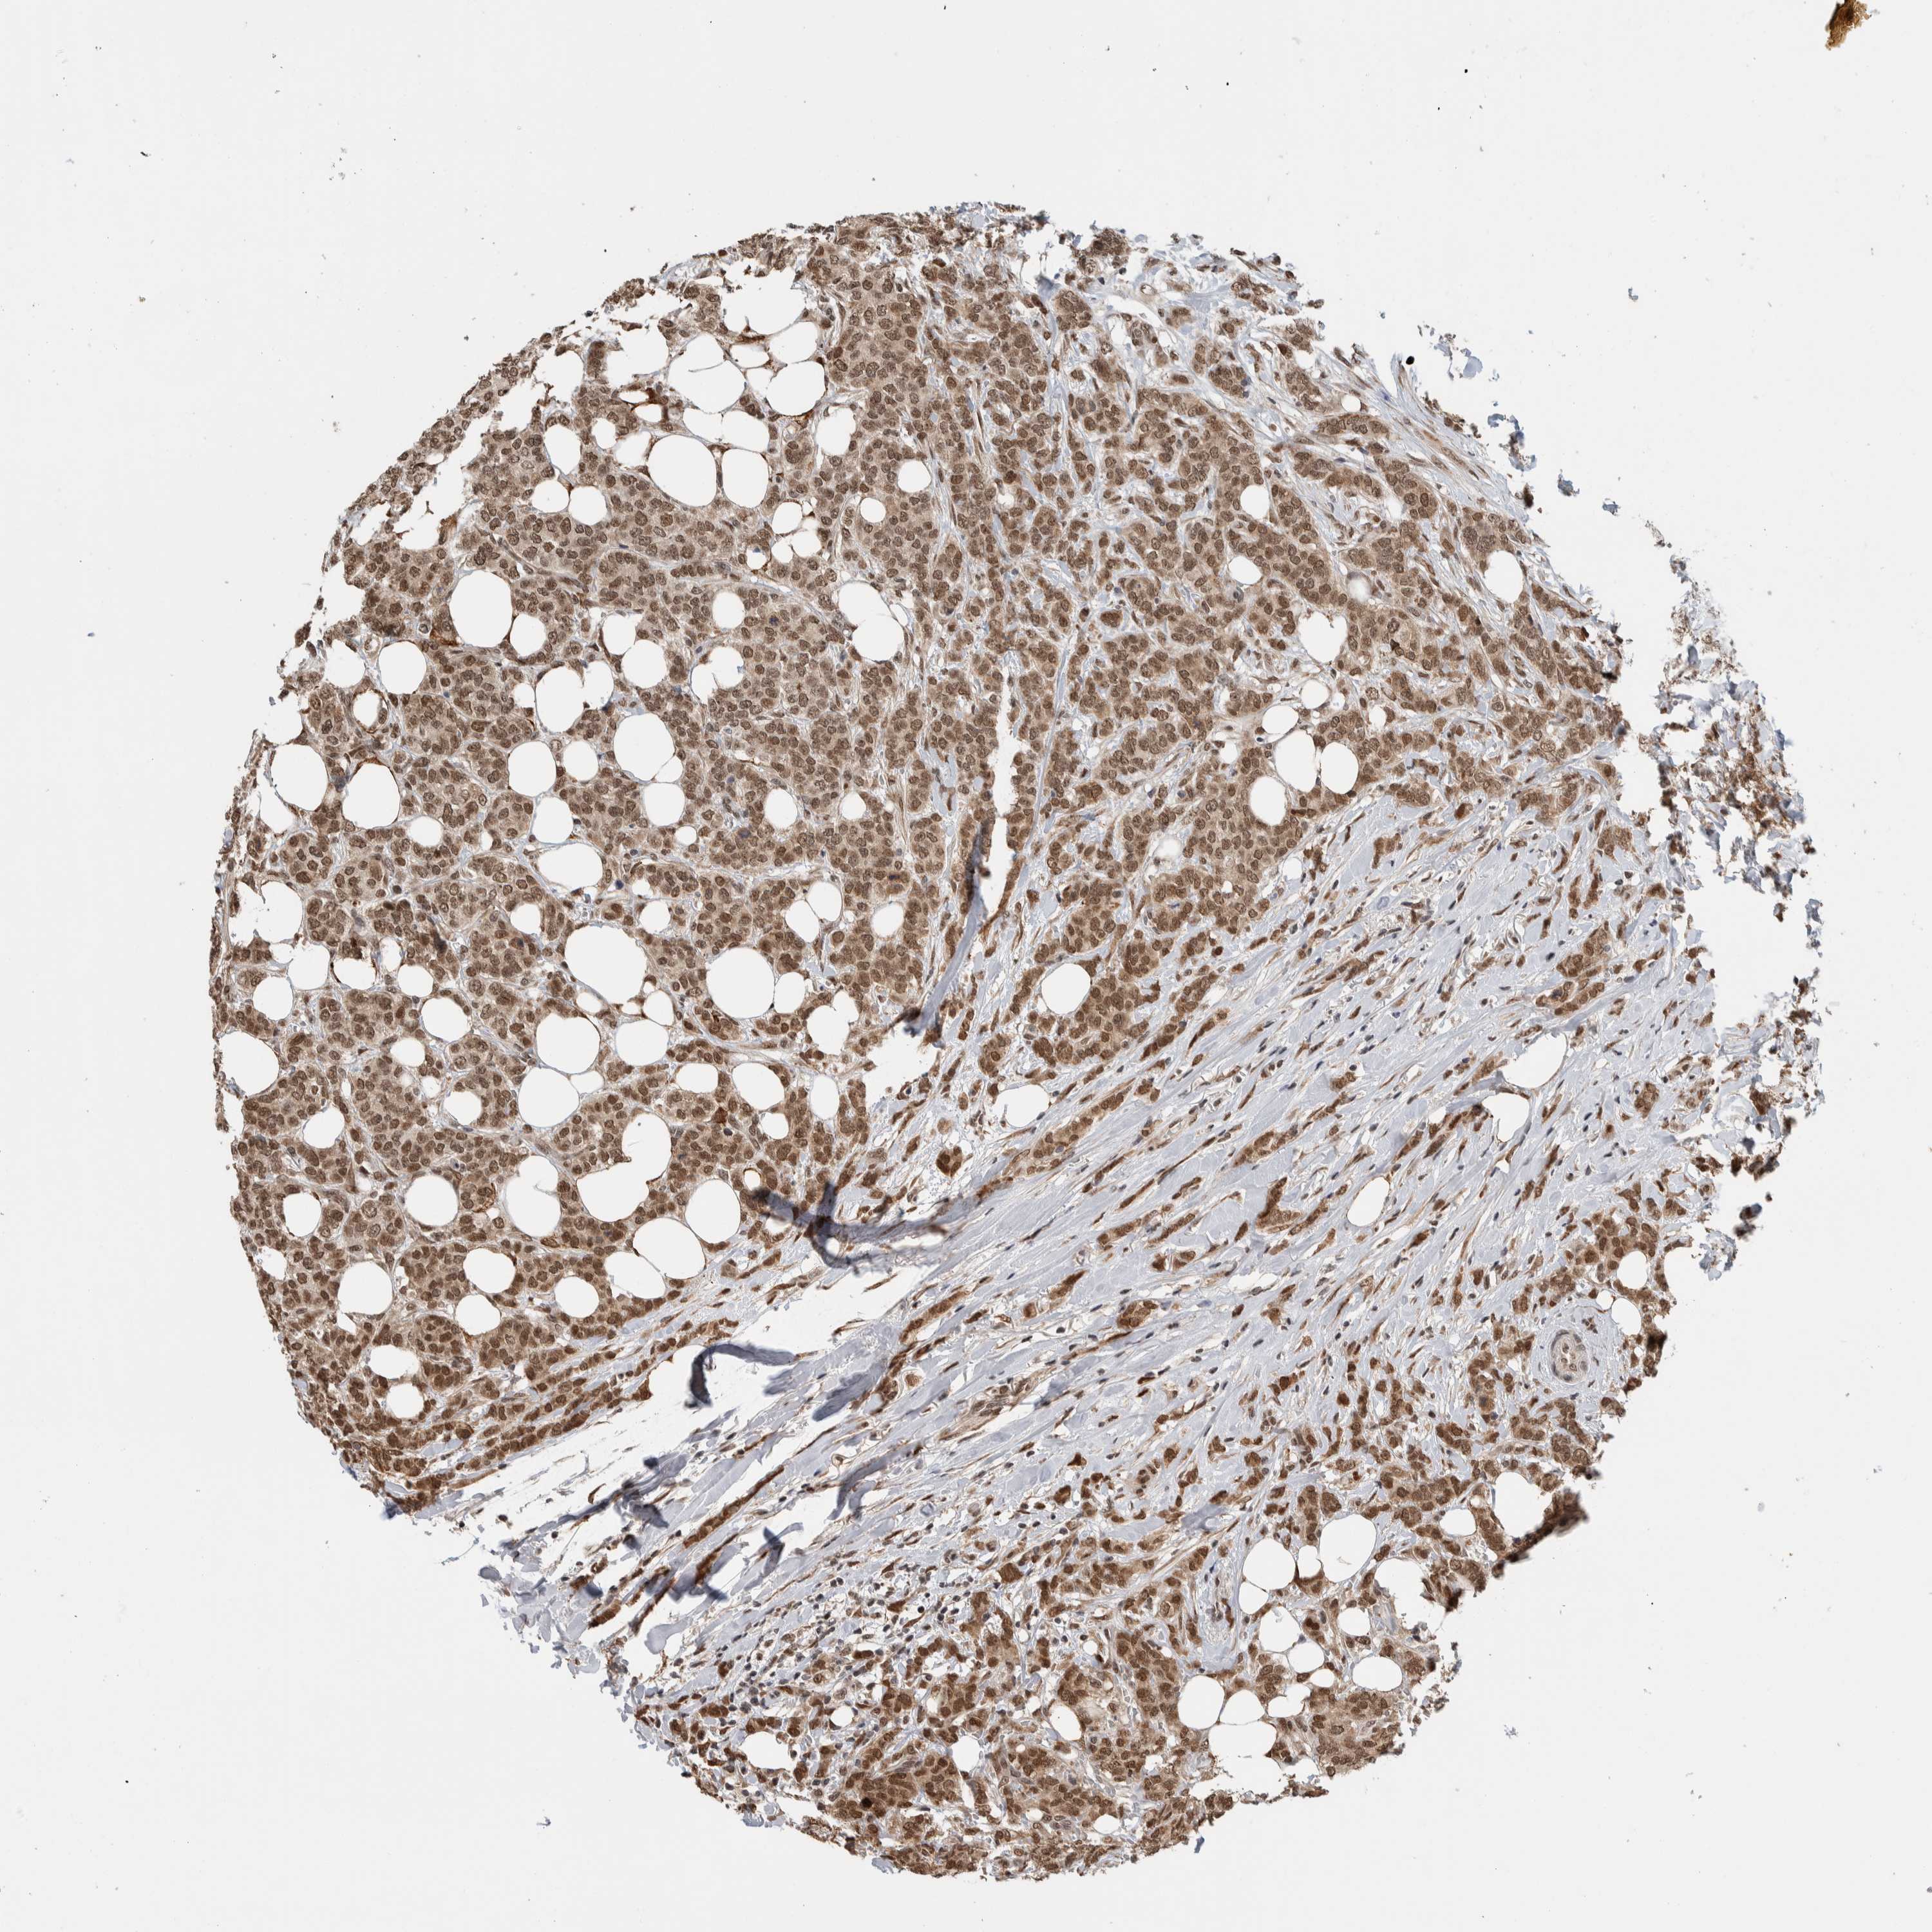

CANCER BREAST CANCER Show tissue menu

BRCA TCGA BRCA VALIDATION PROTEIN EXPRESSION